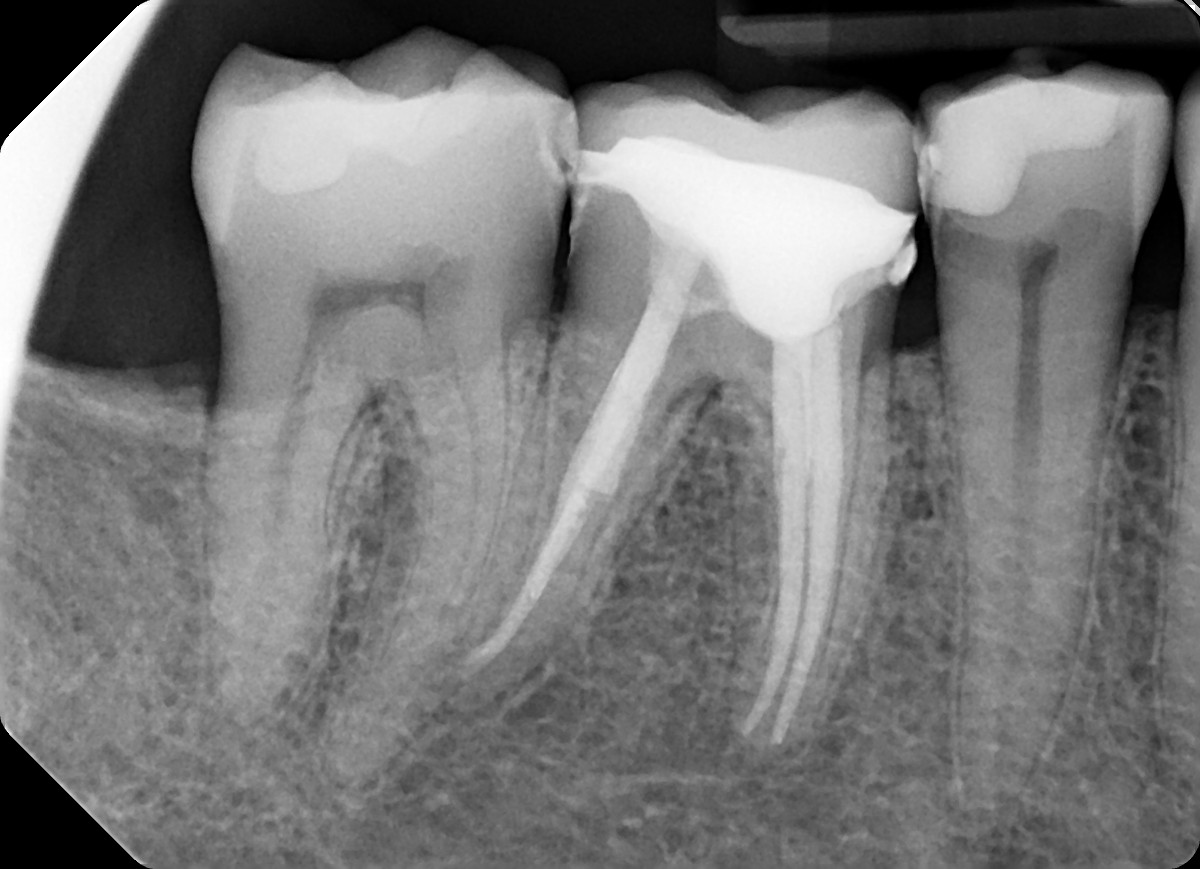

3. What option can describe the post placement in the X ray bellow for the tooth # 3.6?